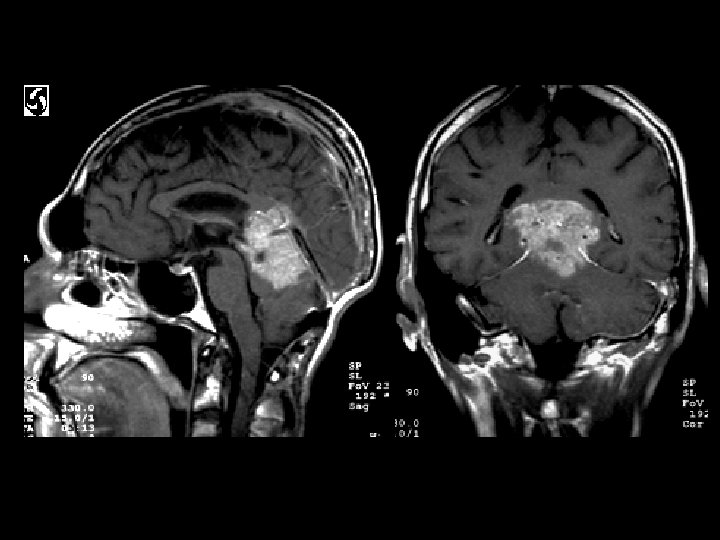

Pinealoblastoma • Findings: – Large, aggressive, enhancing lesion of the pineal region • ddx: – Germinoma – High grade glioma – Metastasis